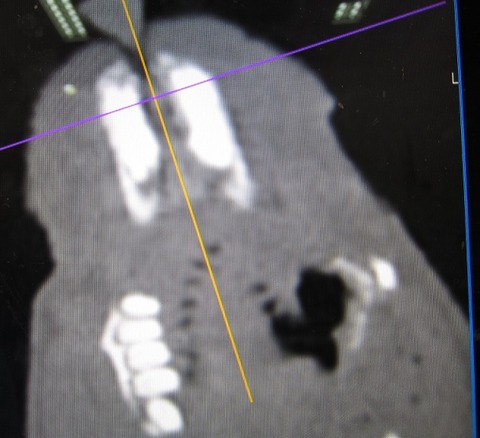

途中経過をCTで

まだまだたくさん残ってますが、👆これが👇こうなります。

完全に取り切れてない部分もありますが、すでに時間もかなりかかっていたのでひとまず終了。